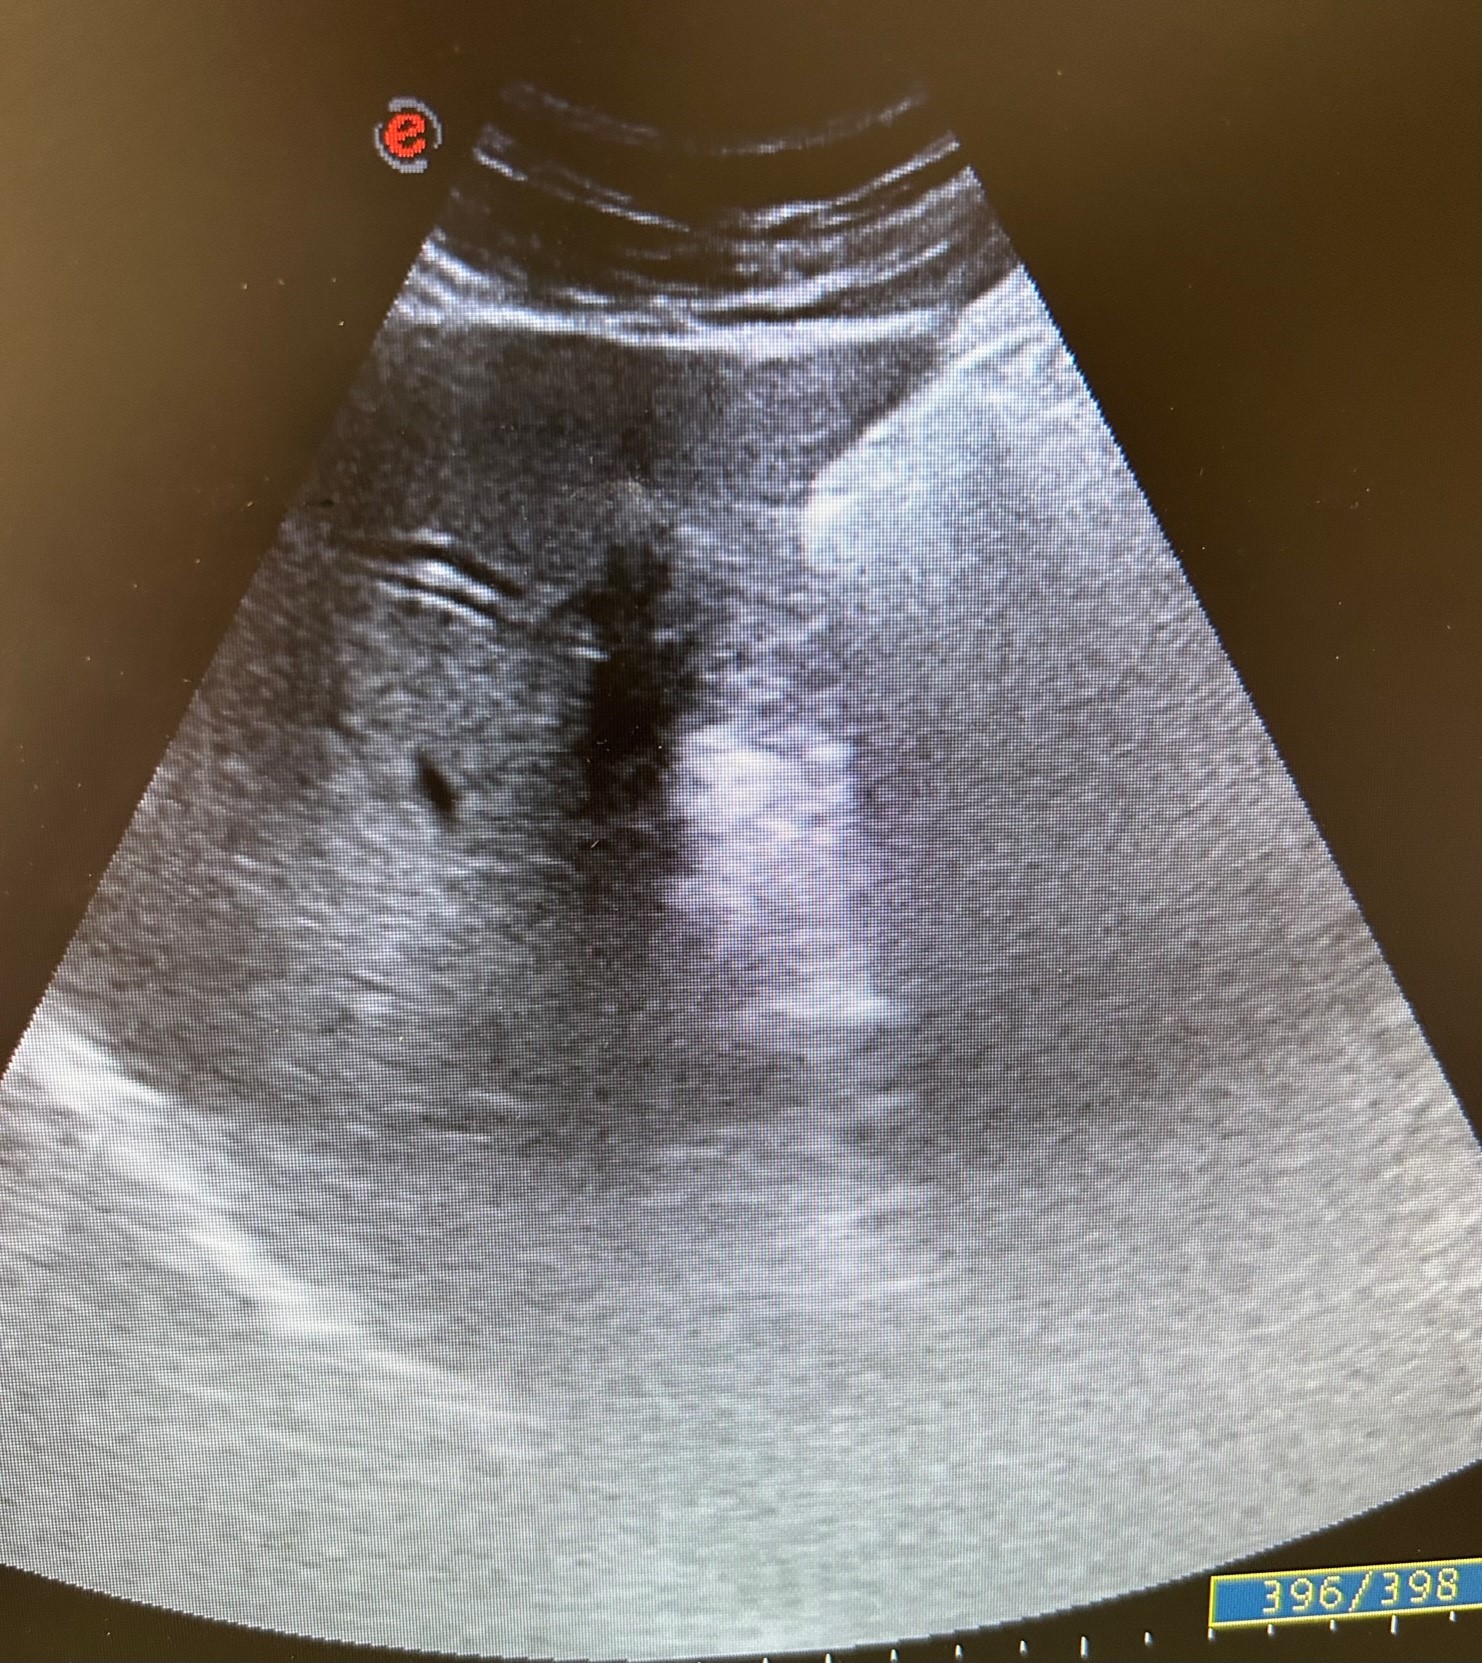

En la ecografía se observa ectasia de la vía biliar intrahepática conformando un patrón de doble carril.

No se visualizan colelitiasis.

Por los hallazgos ecográficos y de la exploración física se decide derivar a urgencias del hospital de referencia ante la sospecha de colecistitis aguda vs coledocolitiasis. En urgencias se realiza ecografía con resultado concordante con la realizada desde Atención Primaria.